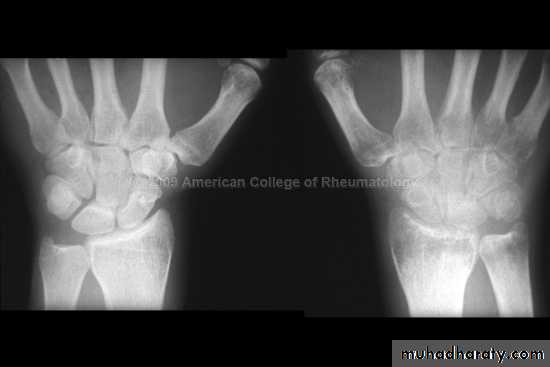

3.Alteration in the shape of the joint.Rheumatoid arthritis :

The changes seen in plain radiograph :Periarticular soft tissue swelling and osteoporosis.

Joint space narrowing .

Bony erosions.

Ulnar deviation.

With severe disease , there may be subluxation at the atlantoaxial joint.